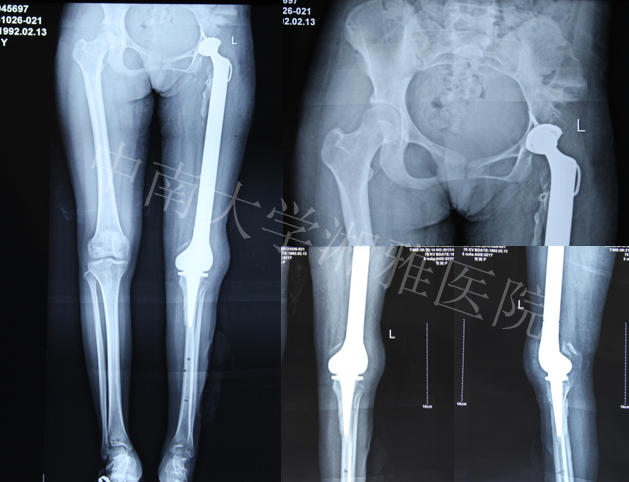

中南大学湘雅医院—全股骨置换病例讨论

患者,女,21岁。

主诉:左下肢短缩,活动不能21年

出生后8个月出现左股骨中段骨髓炎,在当地医院予以保守治疗,1年后好转。其后出现左大腿停止发育,左下肢短缩,行走活动不能。2012年10月至中南大学湘雅医院门诊求治,摄片发现左股骨未发育,收入住院。

入院诊断:左股骨骨髓炎后遗股骨发育不良

2013年4月软组织延长术后

2013年5月髋臼置换

2013年6月安装胫骨侧假体,自制股骨骨水泥占位器占位,继续延长

2013年10月复查双下肢长度恢复

Final Game—2013年10月

术后2月复查—2013年12月